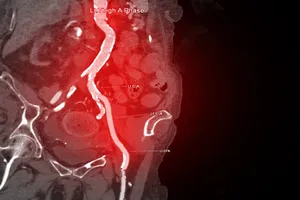

7. 경피적 관상동맥 중재술 (PCI)

막힌 혈관 부위에 작은 절개를 하고 도관을 삽입하여 풍선으로 좁아진 부위를 넓히거나 스텐트를 삽입하여 혈관을 지지하는 시술입니다.

8. 로타렉토미

혈전을 제거하여 혈관을 넓히는 시술입니다.